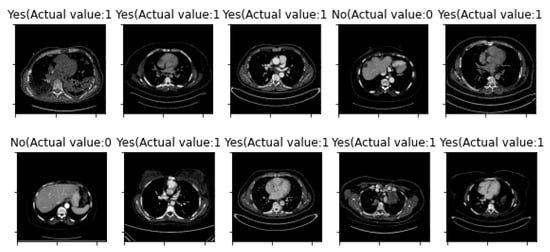

3. Results

| First Run: | Second Run: | ||

| Training Sample Error Rate | 5% | Training Sample Error Rate | 5% |

| Testing Sample Error Rate | 14.586% | Testing Sample Error Rate | 8.091% |

| Accuracy | 85.414% | Accuracy | 91.909% |